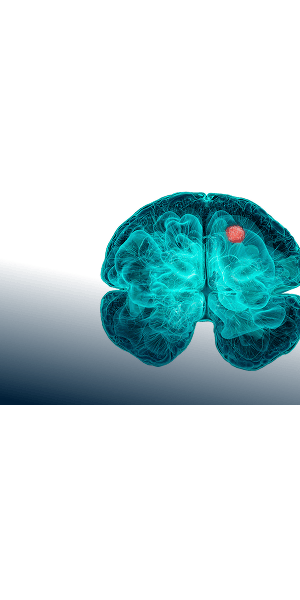

VORANIGO (40 mg tablets) is indicated for the treatment of adult and pediatric patients 12 years and older with Grade 2 astrocytoma or oligodendroglioma with a susceptible isocitrate dehydrogenase-1 (IDH1) or isocitrate dehydrogenase-2 (IDH2) mutation, as detected by an FDA-approved test, following surgery including biopsy, sub-total resection, or gross total resection.

References: 1. Roh TH, Kim S. Supramaximal resection for glioblastoma: redefining the extent of resection criteria and its impact on survival. Brain Tumor Res Treat. 2023;11(3):166-172. doi:10.14791/btrt.2023.0012 2. Voranigo. Package insert. Servier Pharmaceuticals LLC; 2025. 3. Mellinghoff IK, van den Bent MJ, Blumenthal DT, et al. Vorasidenib in IDH1- or IDH2-mutant low-grade glioma. N Engl J Med. 2023;289(7):589-601. doi:10.1056/NEJMoa2304194